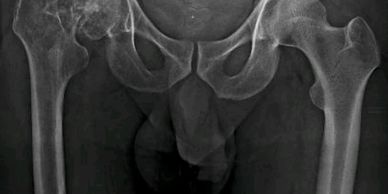

Artroplastía total de cadera bilateral en un tiempo

Paciente de 52 años, con artrosis bilateral de cadera. Se realizó una artroplastía total de cadera bilateral en un tiempo.